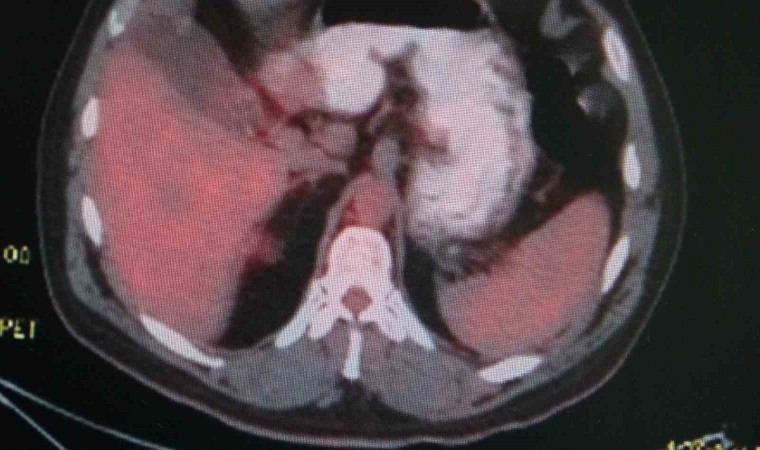

Doç. Dr. Onur Ermerak, "Akciğer kanseri, dünyada kanser nedenli ölümlerde en sık rastlanan ölüm nedenidir. Akciğer kanserinde henüz tarama aşamasına gelemedik. Amacımız o aşamaya gelip erken evrede akciğer kanserini yakalayıp o hastalığı tedavi etmeye başlamaktır. Akciğer kanserinin sigarayla ilişkili olduğunu biliyoruz. Çevre kirliliği, çeşitli kimyasallar akciğer kanserine neden olmaktadır. Maalesef geç bulgu ve şikayet verdiği için hastalar genelde geç evrede yakalanıp tedaviden yarar göremeyecek durumda bize başvuruyorlar. Sadece yüzde 15 hastada sağ kalım görülmektedir. Biz onu çok daha yüksek rakamlara çıkartıp hastalarımıza güzel günler sunmak istiyoruz. Öksürük, istenmeyen kilo kaybı, kanlı balgam, halsizlik, yorgunluk ve iştah kaybı gibi etkilerle görülmektedir. Özellikle kilo kaybı ve geçmeyen öksürük bizim için çok önemli bir bulgudur. Bu hastaların bize başvurmaları gerekir. Burada altını çizmek istediğimiz nokta, tarama programlarıyla sağ kalımda da yüzde 40’lara kadar bir artış sağlamaktayız. Tarama programı, düşük doz tomografilerle hastaları tarayıp bu hastalık daha oluşma aşamasındayken en güzel tedaviyi verip hastaların akciğer kanseri ile baş başa kalmamasını sağlıyoruz. 50 yaş üstünü geçmiş ve 15 yıl sigara tüketmiş hastaların hepsi tarama yapmalıdır. Bizim ülkemizde de aktif sigara kullanımının yanında pasif içicilik de devam ediyor ve biz bu konuyu ciddiye almalıyız. Akciğer kanserine yakalanan hastaların yüzde 90’ı sigara içmekte. Bunların arasında da yüzde 50’si sigarayı bırakmış hastalar oluyor. Hastaların merkezlere başvurup taramasını yapıp hastalığı erken evrede yakaladıktan sonra en uygun tedavilerle sağlığına kavuşmasını amaçlamaktayız. Sigara içmemek çok önemli. Sigara içilen ortamda dahi bulunmamaları çok önemli. Ve farkındalığı oluşturup en ufak bir şüphede gerekli tarama endikasyonlarıyla gidip taranmalarını öneriyoruz. Akciğer kanseri sinsi bir kanserdir, geç bulgu ve şikayet veriyor. Öncelikle sigara içmeyelim ve hastalığın taramasını mutlaka yaptıralım" dedi.